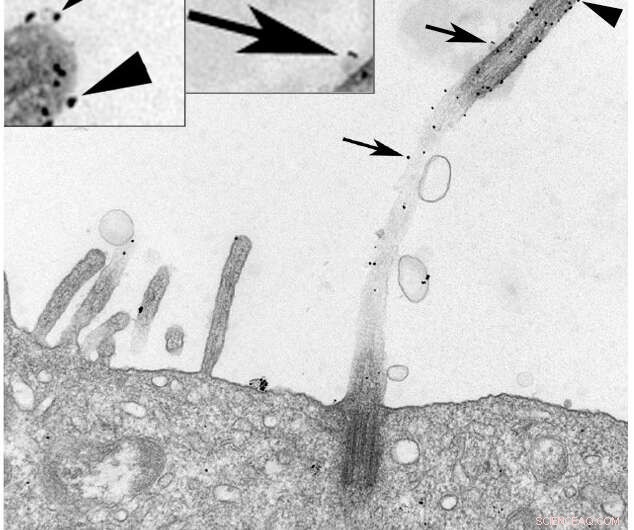

Immunogold labeling of Exoc5-myc (a component of the exocyst) in MDCK cells shows black dots along the primary cilium (arrowheads) and associated vesicles (arrows). The image was taken at 53,400X magnification. Credit: This image was previously published at low magnification in Molecular Biology of the Cell (Zuo, X., Guo, W., Lipschutz, J.H. 2009. Molecular Biology of the Cell. 20:2522-2529) and is used with permission.

Although the cilium has been known to scientists for more than 100 years, it is only recently that it has been acknowledged to play important roles in physiology. Virtually every cell has a primary cilium that functions to senses fluid flow, transmits chemical signals to other cells and controls cell growth. Defects in the function of cilia lead to a class of diseases called ciliopathies, which include polycystic kidney disease, primary ciliary dyskinesia and Bardet-Biedl syndrome.

Extracellular vesicles (EVs), membrane-bound carriers with complex cargos that include proteins, lipids and nucleic acids, function in long-distance cellular communication, but how cilia contribute to EV production was previously unclear to the scientific community. New work from researchers at the Medical University of South Carolina (MUSC), published online on Nov. 6 by the Journal of Biological Chemistry, shows that primary cilia generate approximately 60% of the small EVs produced by renal tubule cells and that manipulation of cilium length affects the production of EVs. Furthermore, the protein content of EVs is very different depending on the length of the cilia.

"For many years, people thought EVs represented a garbage disposal system—a way for the cell to get rid of things it didn't need. But I think it is pretty clear that small (50-150nm) EVs represent one of the main signaling mechanisms of the cell," says Joshua H. Lipschutz, M.D., the Arthur V. Williams Chair and director of the Division of Nephology at MUSC. "This is the first real demonstration in mammalian cells that ectosomes, EVs produced by primary cilia as opposed to exosomes, which are EVs that are similar in size but form in the multivesicular bodies of the cell, are so prominent."